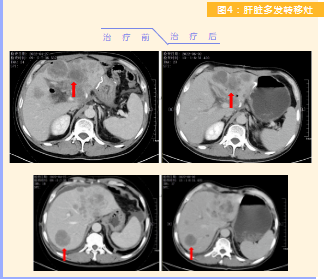

患者完成1周期治療后,上腹部疼痛癥狀基本消失,梗阻性黃疸癥狀緩解,腫瘤指標(biāo)下降(圖1),肺部多發(fā)轉(zhuǎn)移灶消失和縮小(圖2),雙肺門淋巴結(jié)縮小(圖3),肝臟多發(fā)轉(zhuǎn)移灶縮?。▓D4)。